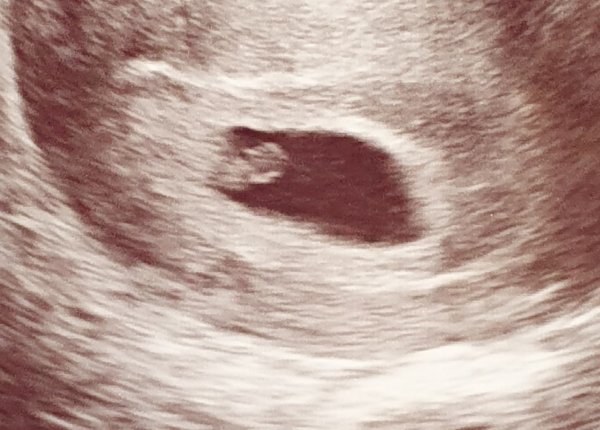

Piti tulla päivittämään oma tilanne: Kävimme toisessa ultrassa. Meidän pieni on kovasti vaikea löytää edelleen, mutta siellä hän näkyi ja hänelle saatiin mitta noin 6,6 mm, joka vastaa viikkoja. Siellä se pieni sykekin hakkasi jo todella voimakkaasti ❤ Kai tähän alkaa jo uskomaan.

20210406_172858.jpg